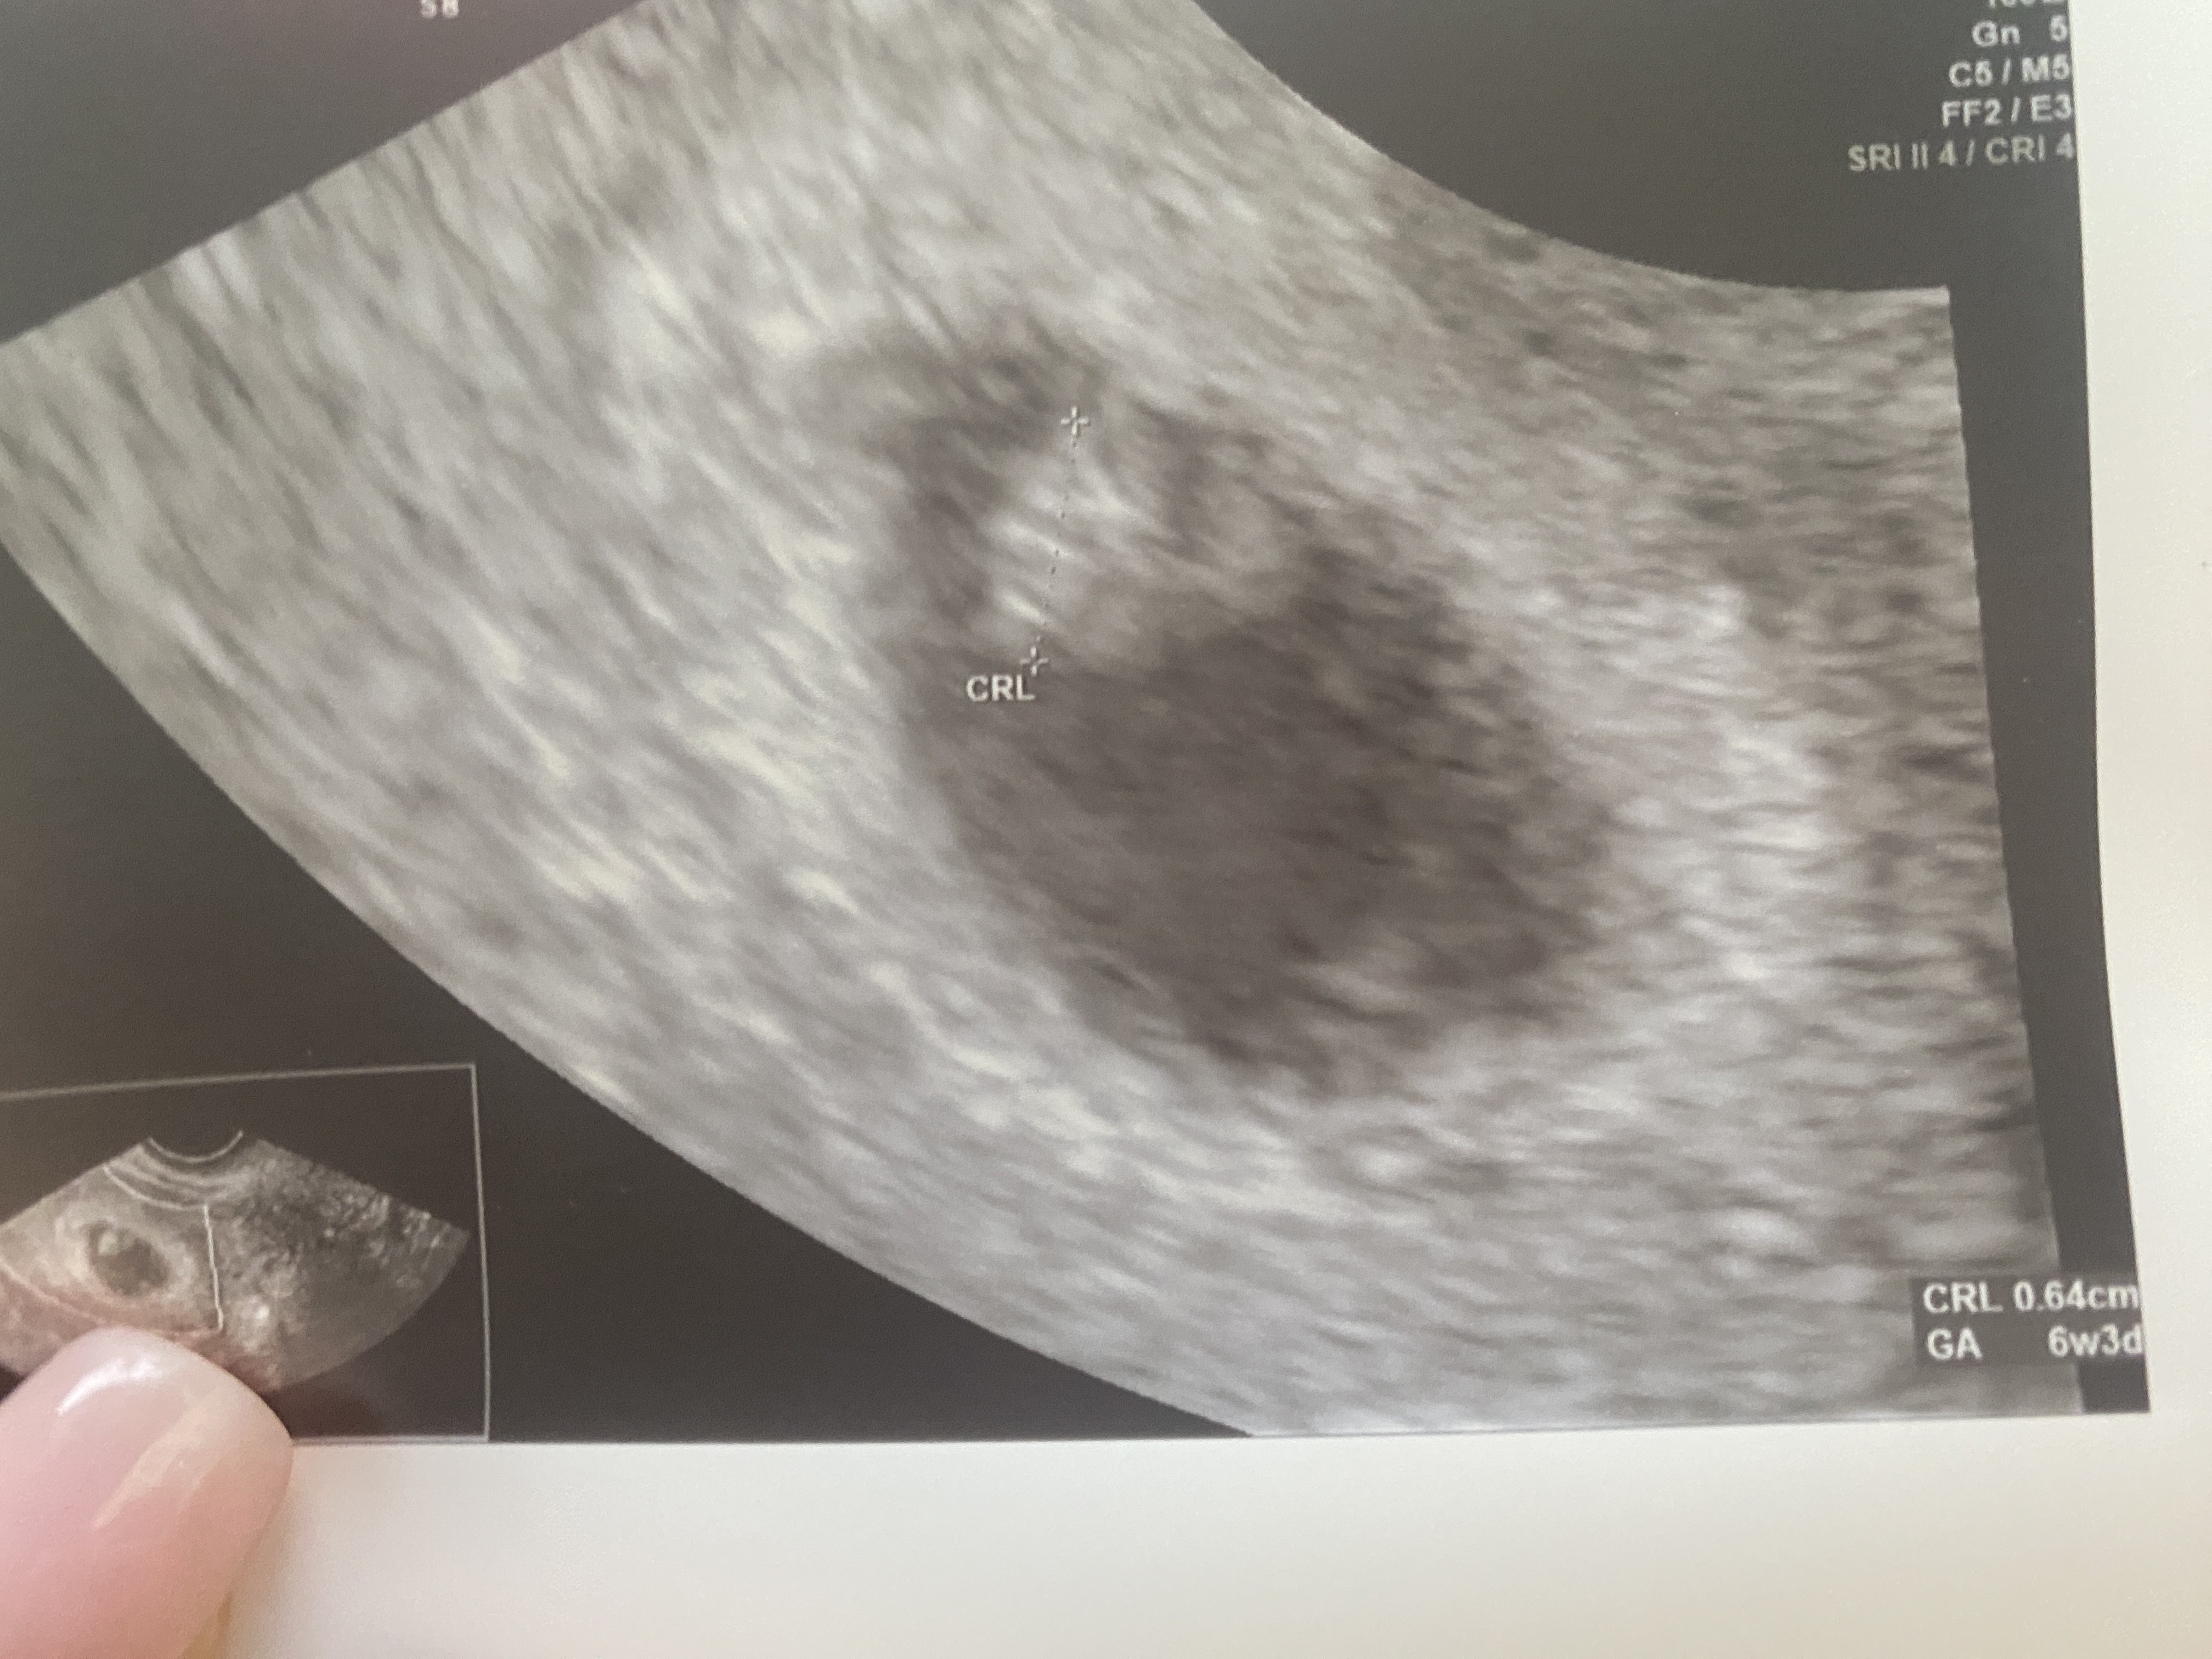

super! a ktory masz tydzien? Ja w czwartek ide i sie zastanawiam czy cos bedzie widac. Mam teraz 5+4.Ja już po wizycie! Mamy serduszko! Już zarodek ma 6,4 mmdziękuje za wszystkie kciuki

Super!! Wspaniała wiadomośćJa już po wizycie! Mamy serduszko! Już zarodek ma 6,4 mmdziękuje za wszystkie kciuki